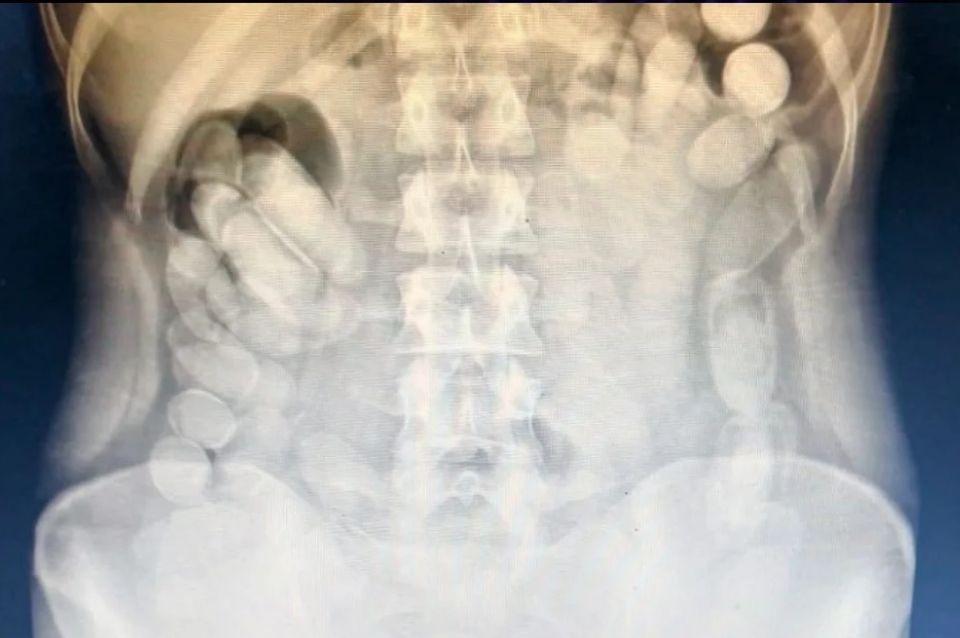

Una vez en el Nosocomio local, se le realizó una radiografía a la mujer mediante la cual se pudo observar la presencia de las dosis en su abdomen. Más tarde, la involucrada evacuó 106 cápsulas.

Tras realizar la prueba de campo Narcotest sobre los 118 envoltorios cilíndricos detectados se obtuvo un resultado positivo para cocaína con un peso total de 1 kilo 388 gramos.